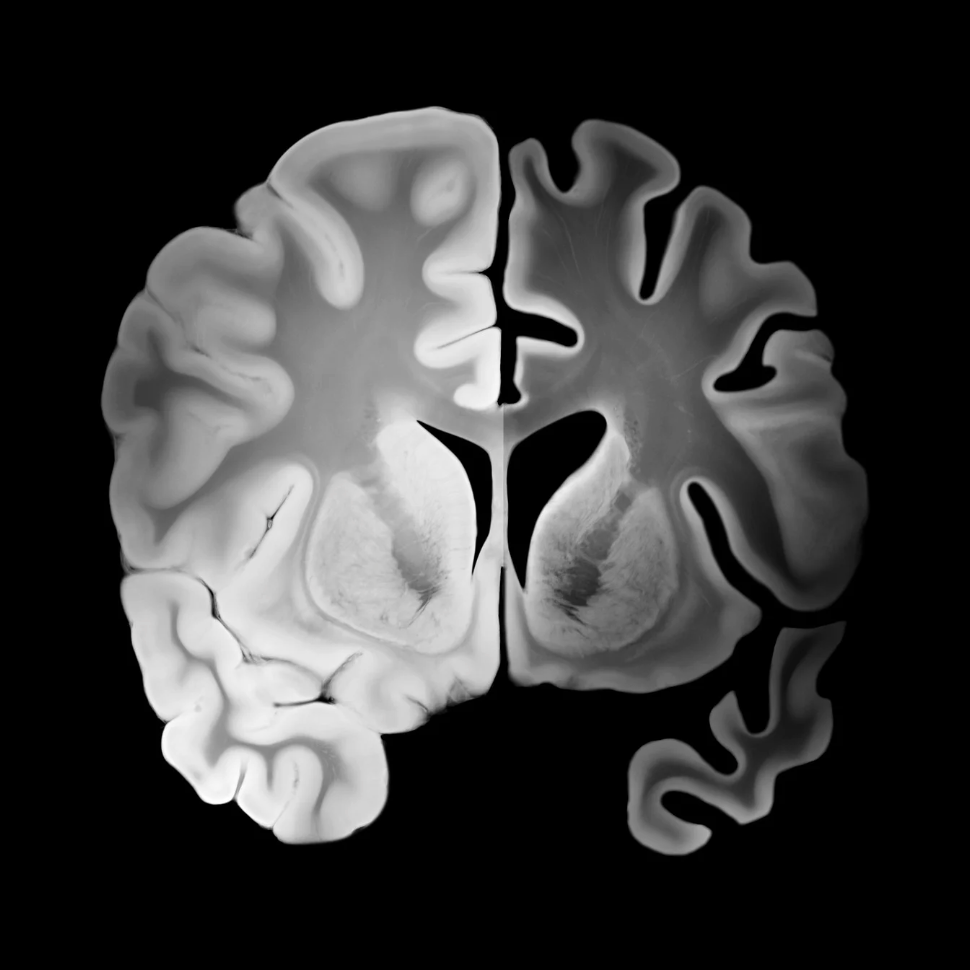

Read MoreNew studies show restoring NAD⁺ may reverse Alzheimer’s disease in animal models and reduce biomarkers in humans. Here’s what the science says.